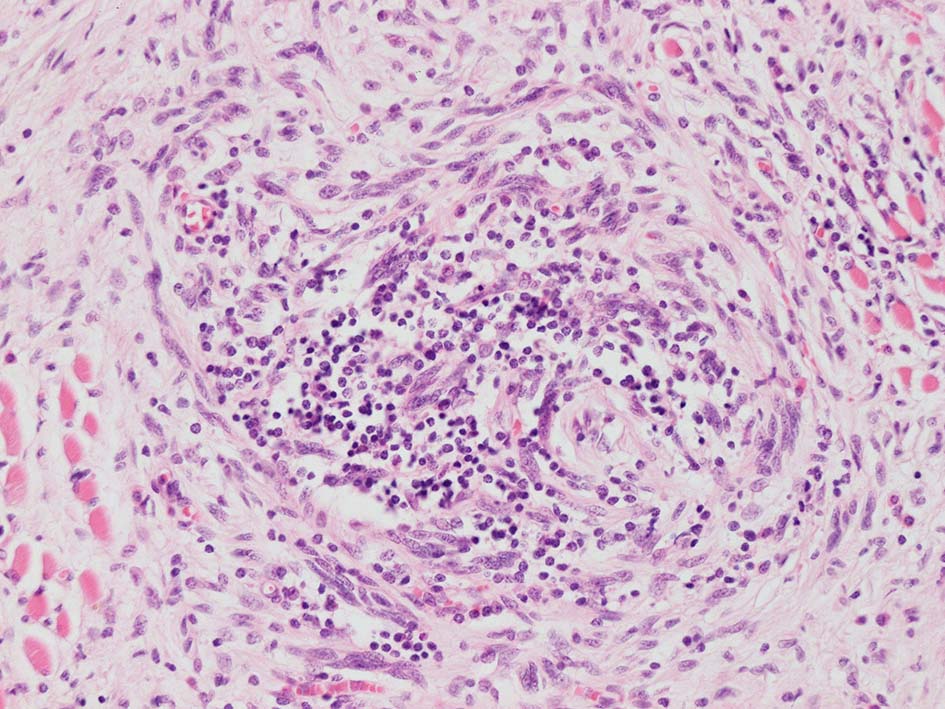

紡錘形異型メラノサイトが著明な間質反応(desmoplasia)を伴い増殖する特殊な色素性病変。*1. desmoplastic neurotropic melanomaは, desmoplastic melanomaのうち神経向性(neurotropism:神経周囲侵襲像)がめだつものでReedら*2が最初に報告した。

いずれも腫瘍細胞の異型性が乏しく, 背景の間質反応がめだつこと, メラニンの存在が目立たないことが特徴である。

リンパ濾胞が細血管周囲に形成され, この部分に異型といえる細胞が増加している(S100+)